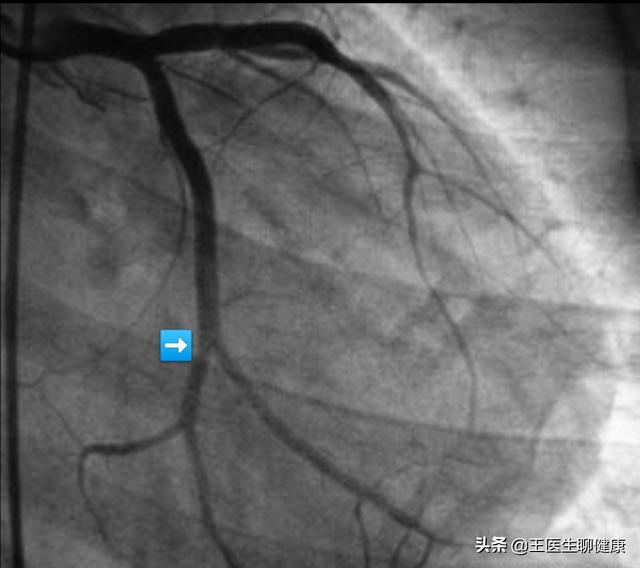

3、冠動脈造影の結果、血管の狭窄度が70%以上であれば、ステント治療を行う必要がある。冠動脈の狭窄の程度が70%以上になると、心筋梗塞の可能性が大きくなるため、ステント留置治療を行うことで、基本的に心筋梗塞のリスクをなくすだけでなく、狭心症の症状を効果的に緩和することができます。

下図は90%以上の冠動脈狭窄で、ステント植え込みで治療しなければ、いつ急性心筋梗塞や突然死が起きてもおかしくない状態である。